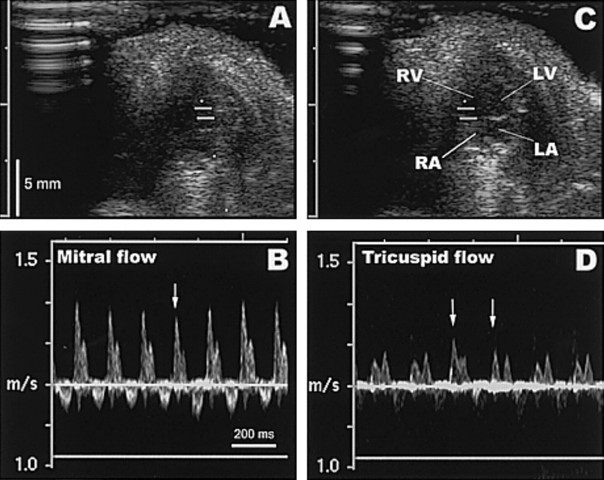

Pulsed Doppler

Imaging blood flow through the chambers and different depths of the heart. Developments including the continuous wave Doppler, spectral wave Doppler and color Doppler ultrasound instruments were discovered.